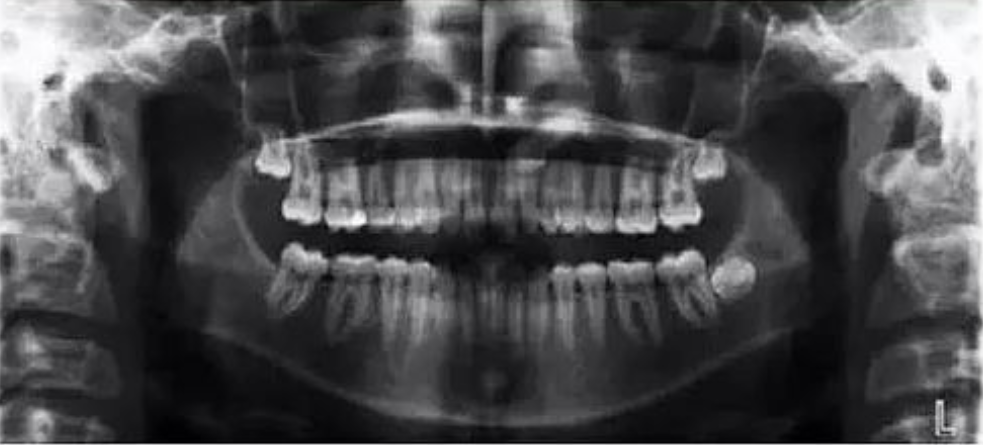

一、下颌前牙区域辐射穿透度不够

【失误原因】

射线被脊柱阻碍,未能完成穿透下颌骨组织。

【解决方法】

调整患者颈部定位,确保颈部直立居中,让患者稍靠前。